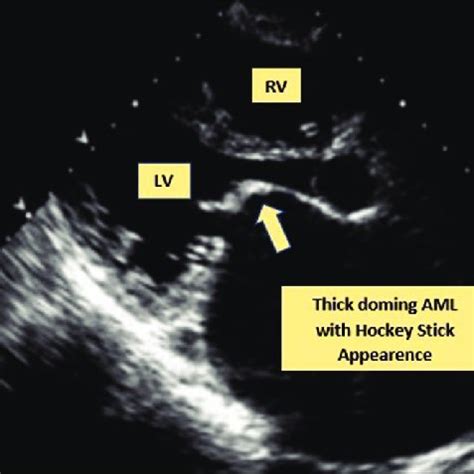

So, what exactly are we looking at when we talk about the hockey stick appearance in the context of Acute Myeloid Leukemia (AML)? Imagine peering through a powerful microscope at a sample of bone marrow or peripheral blood. You’re looking for abnormal cells, known as blast cells, which are immature white blood cells that have gone rogue in AML. Normally, these cells would mature into functional white blood cells, but in AML, they accumulate and don’t mature properly. The hockey stick shape is a specific morphological characteristic that some of these blast cells can display. It’s not just a vague resemblance; it’s quite distinctive. Typically, the nucleus of the blast cell appears elongated and curved, often with a deep indentation or fold. Think of the shaft of a hockey stick. Then, the cytoplasm extends from one end of this nucleus in a tail-like fashion, resembling the blade of the stick. This gives the cell a characteristic, elongated, and slightly hooked appearance. It’s important to understand that not all blast cells in an AML patient will show this morphology, and it’s not present in every single case of AML. However, when it is seen, it’s a significant finding for the hematopathologist. This specific shape is thought to arise from abnormalities in the cell’s cytoskeleton and nuclear structure , which are common features of malignant transformation. The cell loses its normal roundness and develops these irregular, elongated forms due to disruptions in the proteins that maintain cell shape and organization. The presence of the hockey stick appearance can sometimes suggest a particular lineage of AML, most commonly those with monocytic differentiation . This includes subtypes like acute monocytic leukemia (AMoL) or acute myelomonocytic leukemia (AMML). In these types of AML, the myeloid precursors have a tendency to develop more irregular and folded nuclear shapes, making the hockey stick morphology a more frequent observation. Recognizing this shape is crucial because it adds another piece to the diagnostic puzzle. It reinforces the presence of leukemic blasts and can help guide the pathologist in classifying the specific subtype of AML. This classification is absolutely critical, guys, because different subtypes of AML respond differently to various treatments. So, while we have advanced genetic and molecular tests today, the fundamental skill of recognizing classic morphological features like the hockey stick appearance remains a cornerstone of AML diagnosis. It’s a visual hallmark that, when identified by an experienced pathologist, provides valuable information that complements other diagnostic data, leading to more accurate and timely diagnoses and ultimately, better patient care. The detailed examination of cells under a microscope is a skill that has been refined over decades, and these classic descriptions, like the hockey stick appearance, are part of the specialized language pathologists use to describe and classify blood disorders. It’s a testament to the power of observation in medicine.